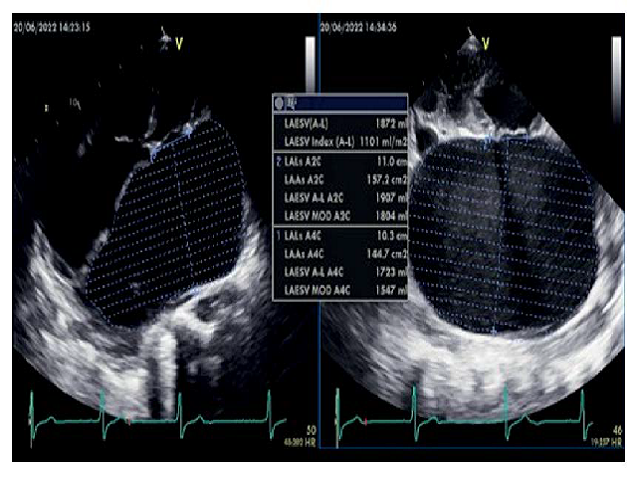

ArticleViewAbstractPharmacognosy Journal,2022,14,6,829-832.DOI:10.5530/pj.2022.14.175Published:December 2022Type:Research Article Erlenmeyer-shaped Heart in a Patient with Giant Left Atrium due to Mixed Mitral Valve Pathology: A Neglected Case in a Rural Area in IndonesiaAprilia Romdiyana, R. Mohammad Budiarto, and Evelyne Chandra Aprilia Romdiyana*, R. Mohammad Budiarto, Evelyne Chandra Department of Cardiology and Vascular Medicine, Airlangga University, Dr Soetomo General Hospital, Surabaya, INDONESIA. Abstract:Giant left atrium (GLA) is a rare condition typically found in patients with rheumatic mitral valve disease. On chest radiographs, this condition often mimics another cause of cardiomegaly. A 52-year-old man was admitted to the hospital with complaints of shortness of breath and orthopnea. Mid-diastolic and grade IV pansystolic murmurs could be heard at the apex radiating to the axilla on cardiac auscultation. The electrocardiogram showed a junctional tachycardia rhythm, while the chest radiograph displayed extreme cardiomegaly with Erlenmeyer-shaped heart. Massive pericardial effusion was suspected. Transthoracic echocardiography (TTE) was then performed, revealing GLA with a left atrial volume index (LAVi) of 1101 ml/m2. Meanwhile, transoesophageal echocardiography (TEE) confirmed calcification of P2 and P3 extending to the border of the mitral leaflet up to one third of the chordae tendineae, with moderate mitral stenosis and eccentric mitral regurgitation jet due to prolapse of A2. The patient was treated with optimal medical therapy while awaiting cardiac surgery. GLA is a rare complication of mitral valve disease and an almost forgotten cause of cardiomegaly. Diagnostic imaging procedures with echocardiography are a less invasive and readily available modality to establish the diagnosis of cardiomegaly. Keywords:Erlenmeyer-shaped heart, Giant left atrium, Junctional tachycardia., Mitral regurgitation, Mitral stenosisView:PDF (421.72 KB) PDF Images Transthoracic echocardiographic (TTE) examination showed an extremely huge left atrium of 13.9 mm x 12.3 mm on the apical four-chamber view with LAVi of 1101 ml/m2. ‹ Prostate Cancer: Causes and Medicinal Plants Used in Africa for Twenty Years (2001-2021) up Prediction of MMP-9 Polymorphism Impacts on MDR-TB by Molecular Simulation and Network Interaction ›